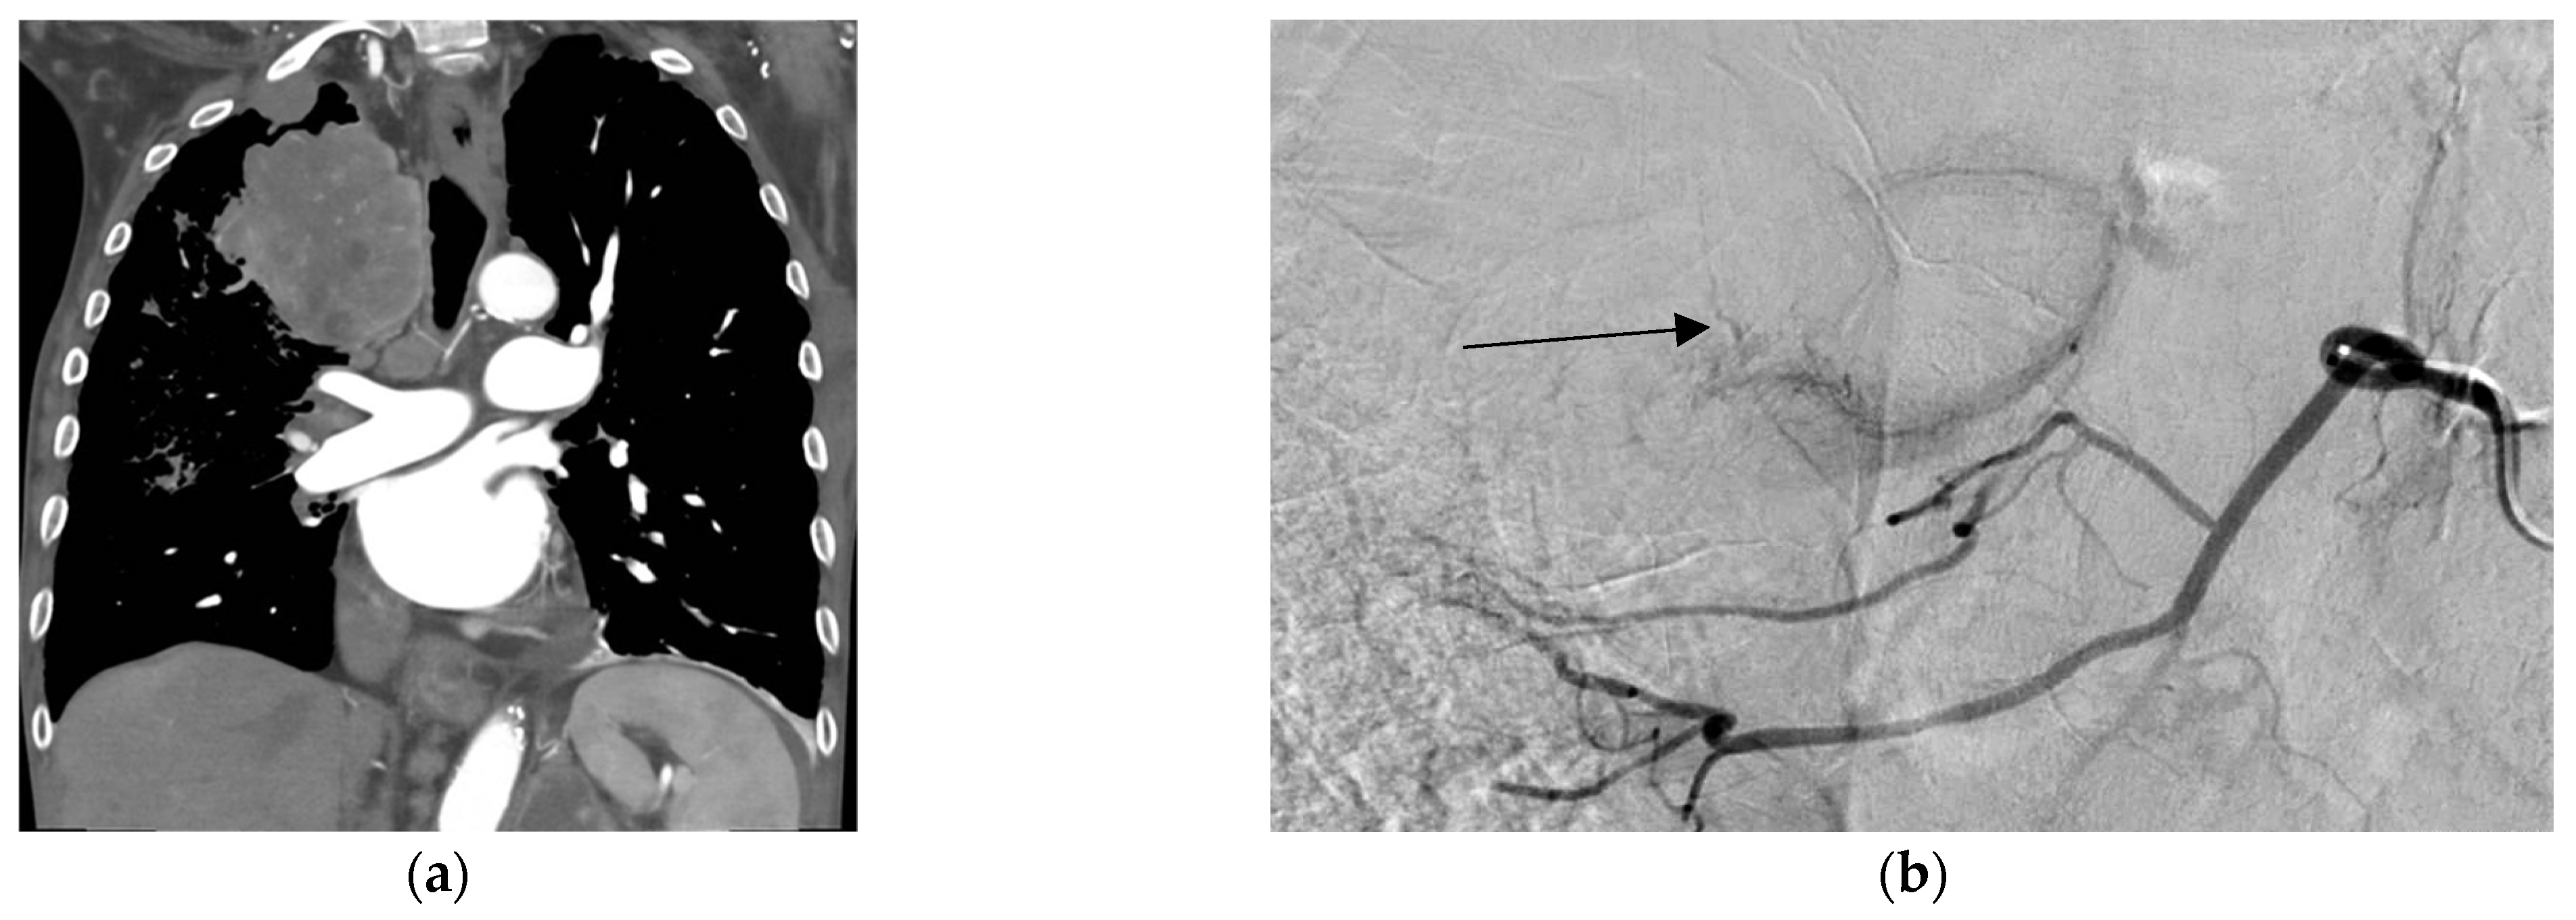

7. Advances in Transarterial Chemoembolization

- Zhang, F.; Liu, Y. Transcatheter Arterial Chemoembolization for Lung Malignant Tumors. Front. Oncol. 2025, 15, 1551644. [Google Scholar] [CrossRef]

- Vogl, T.J.; Mekkawy, A.; Thabet, D.B. Intravascular Treatment Techniques for Locoregional Therapies of Lung Tumors. RöFo 2023, 195, 579–585. [Google Scholar] [CrossRef]

- Xu, S.; Li, Y.-M.; Bie, Z.-X.; Li, X.-G. Drug-Eluting Beads Bronchial Arterial Chemoembolization/Bronchial Arterial Infusion Chemotherapy with and without PD-1 Blockade for Advanced Non-Small Cell Lung Cancer: A Comparative Single-Center Cohort Study. Quant. Imaging Med. Surg. 2023, 13, 6241–6256. [Google Scholar] [CrossRef]

| Bronchial Artery Chemoembolization (BACE) | |||||

| Zhao et al. [21] | Prospective multicenter study of DEB-BACE for refractory NSCLC | 43 | 2-month DCR 95.35% Median OS 11.5 months | Small sample size, no control group, heterogeneous patient and tumor population | DEB-BACE showed high short-term control and symptom relief with grade 1–2 AEs |